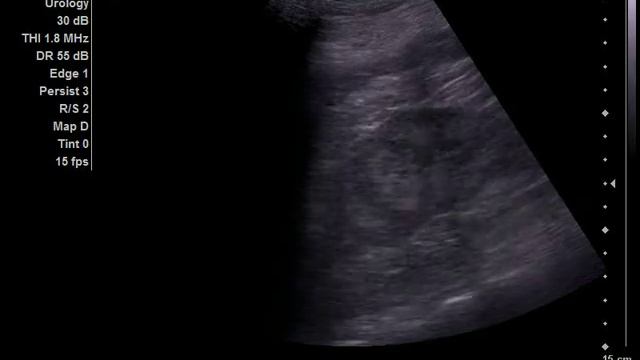

Симптом гиперэхогенных пирамид

Видео: Симптом гиперэхогенных пирамид